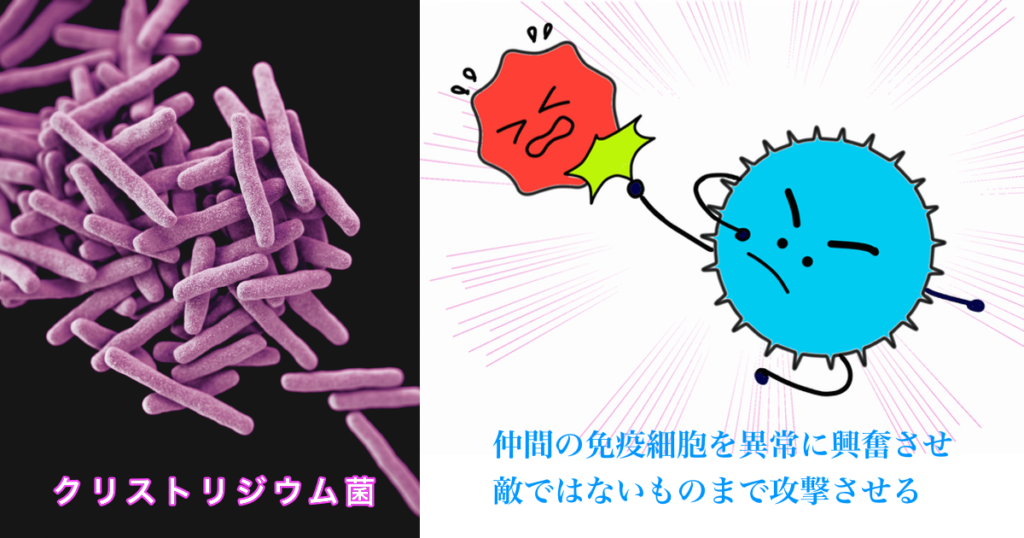

暴走する免疫細胞

私たちの腸には免疫細胞(マクロファージ、Tレグ細胞、Bリンパ球、NK細胞)がありますが、暴走してしまうことがあります。これが本当に始末に悪いんですね〜。味方まで攻撃して手に追えなくなってしまいます。

暴走を食い止めてくれるTレグ細胞

しかし、免疫細胞の暴走を食い止めてくれる存在があります。

17種類のクロストリジウム菌がTレグ細胞(免疫のブレーキ)の免疫細胞の暴走を鎮める物質を放出し、Tレグ細胞を応援します。

※嫌気性細菌であるクロストリジウム感染症もあり、今までは悪玉の代表とされてきたが、最近はTレグ細胞を活性化させるとされている。クロストリジウム菌は、適度な数で良くも悪くもなる。

一部ではアトピーには、クロストリジウム菌を取ってしまった方が早いんじゃないかと言われるようになっています。